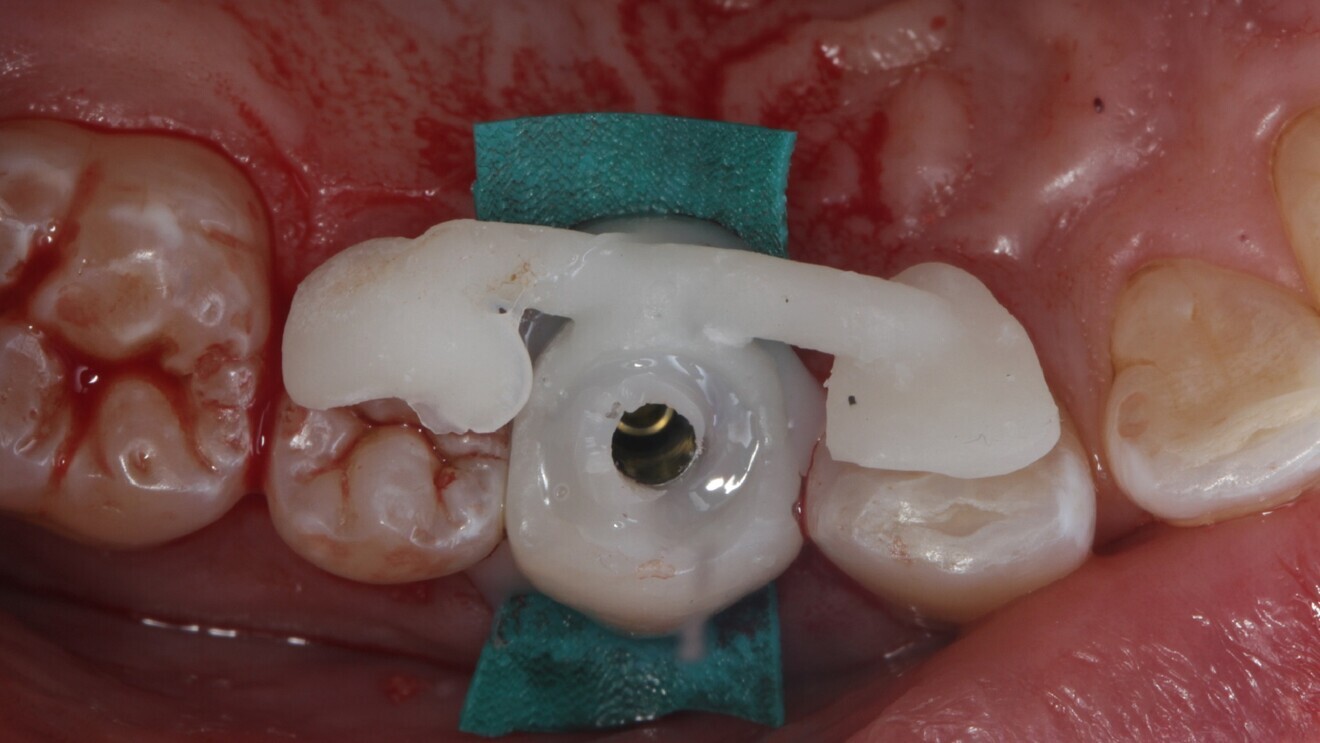

Fig. 10: Intra-oral chairside pick-up of the 3D-printed shell provisional restoration.

Intra-oral scans of the patient’s preoperative condition and the tooth shape from the CBCT scan were utilised to recreate the restorative profile. This process allowed for the fabrication of a 3D-printed shell that closely replicated the original profile (Figs. 9 & 10). This shell was characterised using a stain and glaze system (Rodin Palette Naturalizing Kit, Pac-Dent) to harmonise with the aesthetics of the adjacent teeth. By creating the ideal profile, the soft tissue was adequately supported, preventing any loss of papillary height or soft-tissue contour changes (Fig. 11).